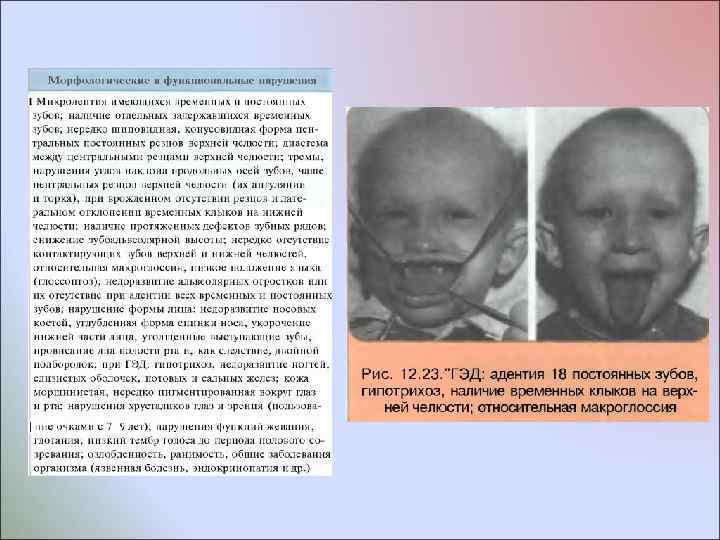

Врожденное отсутствие более 10 постоянных зубов У некоторых пациентов отмечают врожденное множественное отсутствие зубов без изменения развития других производных эктодермы У пациентов с ГЭД мало волос, они светлого цвета, брови недоразвиты, ресницы растут кустиками; кожа сухая, морщинистая, нередко пигментированная вокруг глаз и рта; ногти деформированы; зрение нарушено - пользуются очками с детства. По эстетическим отклонениям, состоянию психоневротического статуса и общим нарушениям организма пациенты этих двух групп различаются. Общим для них является лишь врожденное отсутствие зачатков более 10 постоянных зубов

Врожденное отсутствие более 10 постоянных зубов У некоторых пациентов отмечают врожденное множественное отсутствие зубов без изменения развития других производных эктодермы У пациентов с ГЭД мало волос, они светлого цвета, брови недоразвиты, ресницы растут кустиками; кожа сухая, морщинистая, нередко пигментированная вокруг глаз и рта; ногти деформированы; зрение нарушено - пользуются очками с детства. По эстетическим отклонениям, состоянию психоневротического статуса и общим нарушениям организма пациенты этих двух групп различаются. Общим для них является лишь врожденное отсутствие зачатков более 10 постоянных зубов